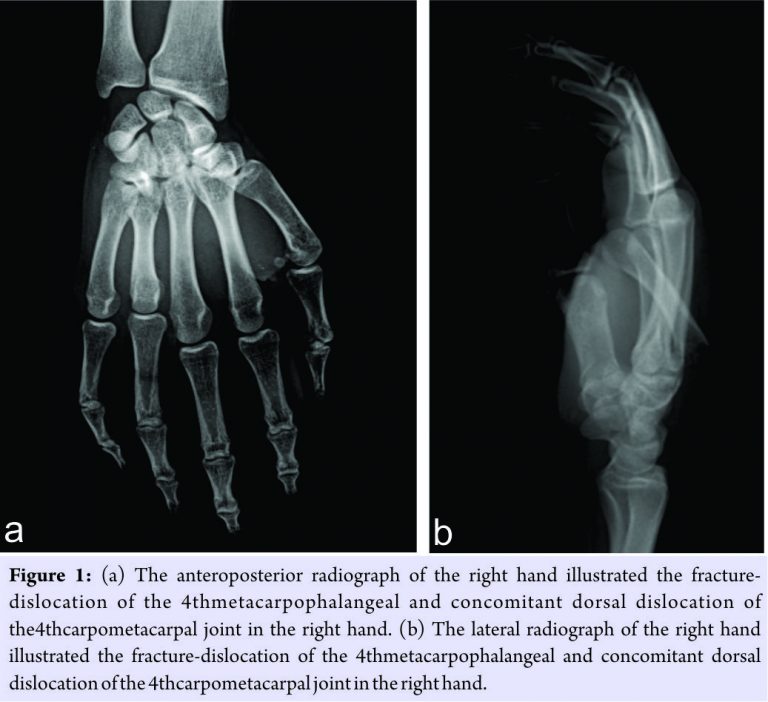

A 17-year-old male was referred to the emergency department of our institute due to multiple traumas following a car accident. At the time of admission, with Glasgow Coma Score of 9,the patient was sleepy and had mismatched pupil sizes. Physical examination revealed that intense pain, gross swelling, and considerable deformity in the 4th finger (ring finger) of the right hand in addition to multiple scalp lacerations. Then, a comprehensive emergency imaging was rendered to the patient, including cranial, thorax, and abdomen. Furthermore, extensive radiographs of the right hand were obtained (Fig. 1a and b).

With an incidence of 1%, CMC fracture-dislocations are particularly rare within whole hand injuries. These challenging disorders are opened to miss in the emergency departments since they frequently occur in poly traumatic patients, and to a great extent, physicians focus on other life-threatening injuries rather than CMC joint dislocations [3]. Therefore, high clinical suspicion and adequate plain radiographs of the hand are required to facilitate the diagnosis of of CMC fracture-dislocation injuries [4,5]. Otherwise, physicians may have to confront some detrimental complications, including pain, weak grip strength, and degenerative arthritis [3]. As an example, Henderson and Arafa reported significant functional disabilities relevant to neglected CMC joint fracture-dislocations in three patients [6]. Considering the presentation of our case, a swollen hand raised suspicion of a likely hand trauma in addition to life-threatening condition, namely, CMC fracture-dislocation.Consequently, additional anteroposterior and lateral radiographs of the hand depicted simultaneous dorsal dislocation of the MCP joint and fracture-dislocation of the CMC joint of the ring finger. A number of studies illustrated that CMC fracture-dislocations tend to dislocate to dorsal side and more commonly result from high-energy traumas such as car accidents [6,7]. Moreover, any case report similar to present injury has yet to be reported to date, addressing CMC fracture-dislocation of the ring finger and concomitant volar MCP joint dislocation in the same finger. While non-operative treatment occupies a considerable place in the management of both phalangeal and metacarpal fractures2, closed reduction and percutaneous fixation or open reduction and internal fixation, plays a pivotal role for irreducible fracture-dislocations.[8]Present studies relevant to this issue suggested that open reduction was essential for the cases of fracture-dislocation [6,7,9,10]. In the light of above treatment concept, considering both concomitant cranial trauma and being reducible and stable of the present injury, we preferred the non-operative treatment. As a result, satisfactory results were accomplished both radiographically and functionally.